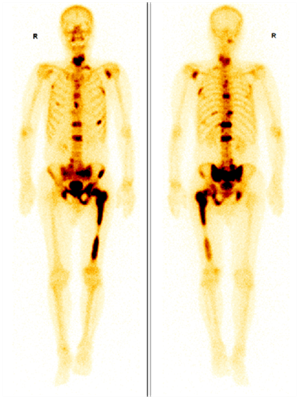

圖示,前列腺癌多發骨轉移,圖中深顏色區域為轉移灶。